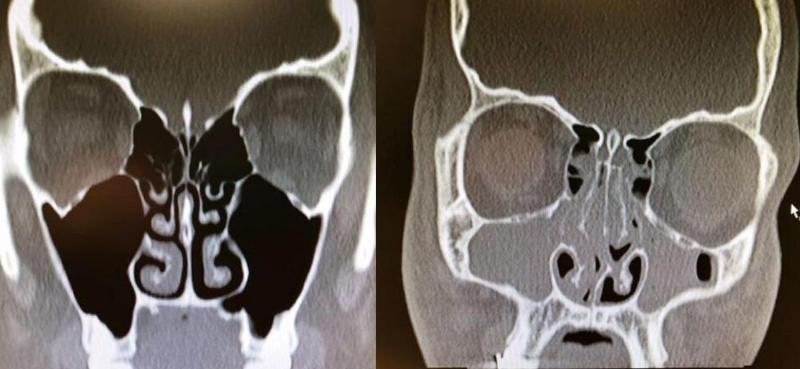

Xrays Of Congested And Un-congested Sinuses Will Make You Grateful For Air

This is really wild. This person had bad congestion and allergies so their sinuses were completely swelled up.

If this doesn't make you breathe a little easier then I don't know what will because I am feeling thankful for my un-congested sinuses right now.